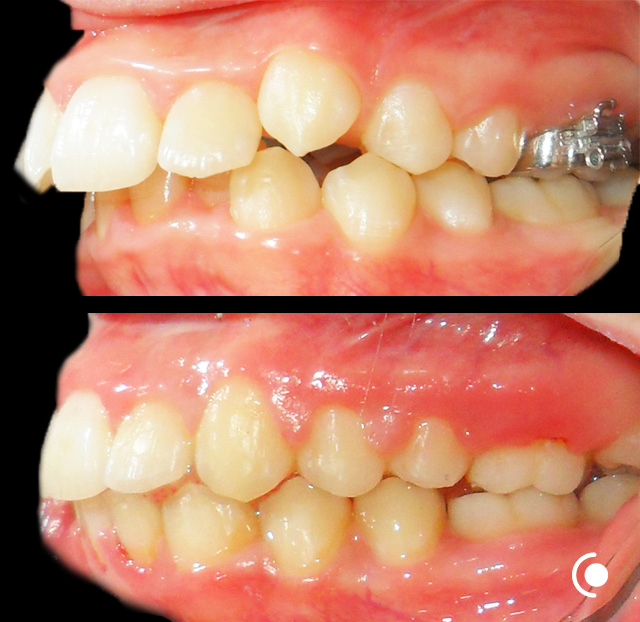

O našoj kvaliteti najbolje govore naši rezultati!